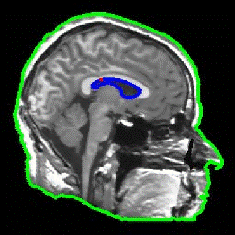

Pengolahan citra medis telah menjadi bidang yang semakin penting dalam dunia kedokteran modern. Salah satu teknik yang digunakan dalam pengolahan citra medis adalah segmentasi, yaitu proses pemisahan objek atau struktur yang ingin diidentifikasi dari latar belakang citra. Dalam kasus citra kepala MRI (Magnetic Resonance Imaging), segmentasi dapat membantu dokter dalam mendiagnosis dan memahami kondisi pasien dengan lebih baik. Salah satu metode yang digunakan dalam segmentasi citra kepala MRI adalah metode Active Contour.

Citra kepala MRI menyediakan informasi rinci tentang struktur otak, jaringan lunak, dan abnormalitas potensial lainnya dalam area kepala. Namun, citra-citra ini sering kali penuh dengan noise dan memiliki kontras yang bervariasi, membuat tugas segmentasi menjadi tantangan yang kompleks. Metode Active Contour, juga dikenal sebagai “Snake” atau “Level Set”, adalah salah satu metode yang membantu mengatasi tantangan ini.